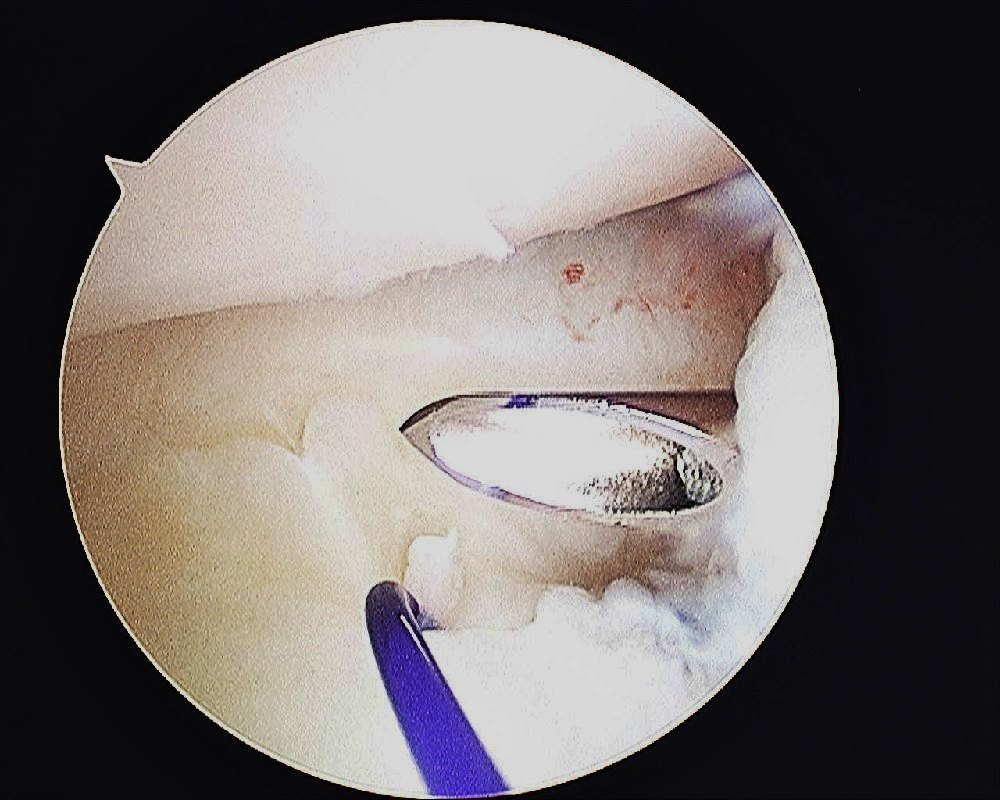

The cannula is passed into the joint again to pass a suture shuttle. I use the PDS 3/0 as a suture shuttle.

The 1st PDS suture that was passed through the TFCC is shuttled back into the joint and out of the capsule.